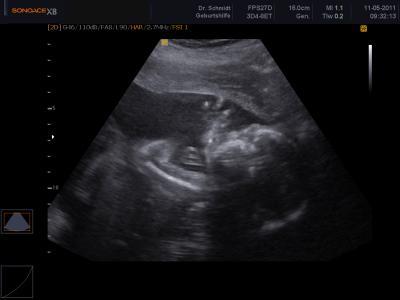

Das schon Wahnsinn .. erst noch sooo winzieg und jetzt sieht man schon alles ... das ist unser Muckie wissen nur leider noch nicht was es wird

Tolles Bild^^ Ich find das faszinieren wie man die Nase und das alles so gut sehen kann^^ Habt ihr einen Wunsch vom Geschlecht her?